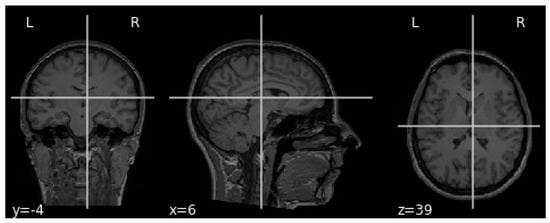

The MRI requires the setup of specific parameters, including radio-frequency pulse and gradient. T1 and T2 sequences are usually used in practice, with both providing specific information about the observed tissue. This research uses the T1 sequence. To reduce the amount of images required for the healthy brain, six sections were chosen from MRI images. A healthy brain sample is shown in Figure 3.

To help distinguish the tumor tissue and more precisely determine the tumor borders, the patients are typically injected with a contrast solution (Gadolinium). These images can be utilized in the classification of the tumor grade. Figure 4 shows axial MRIs with Gadolinium infusion of three grades of glioma brain tumors. Finally, Figure 5 shows three brain tumor cases from the second dataset utilized in this research [81]. As mentioned, all employed images were normalized to the [ 0 , 1 ] interval, and their dimension was set to 128 × 128 pixels.